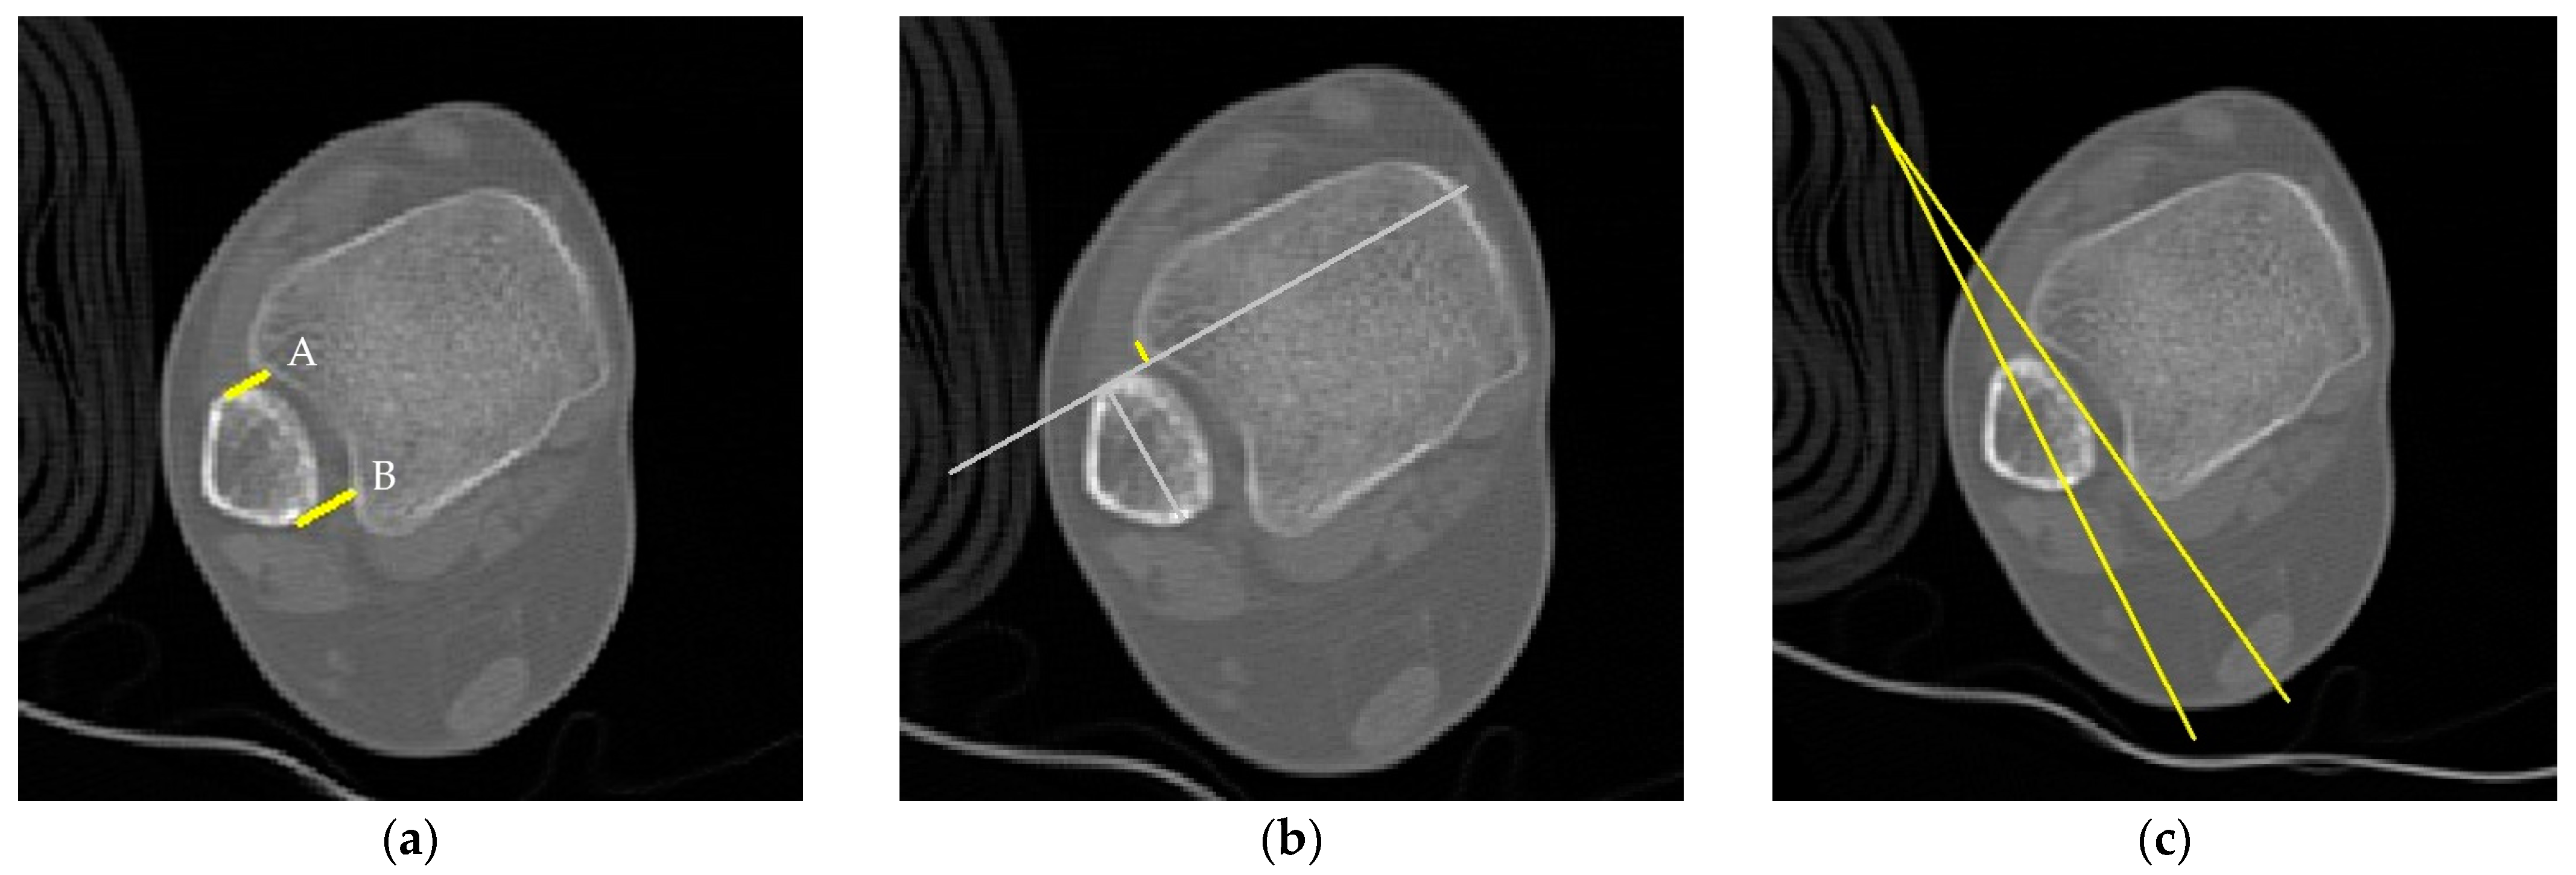

| Direct Anterior Difference | This is the perpendicular distance measured from the incisura to the anterior end of the fibular orientation line. |

| Direct Posterior Difference | This refers to the perpendicular distance from the incisura to the posterior end of the line representing the fibular orientation. |

| Fibular Translation | This is the distance measured between the anterior border of the tibial incisura and a line representing the direct anterior difference. It is considered positive when the fibula is situated behind the anterior border of the incisura. |

| Fibular Rotation | This is the angle formed between a line connecting the anterior and posterior borders of the tibial incisura and another line on the fibula indicating its orientation. This angle is deemed positive when the fibula is internally rotated relative to the incisura. |